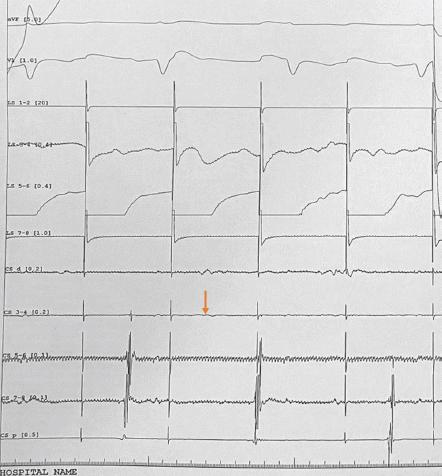

Figure 4